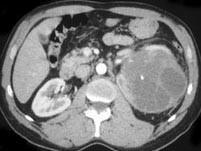

问题 女,48岁,左腰部胀痛不适2个月余,请根据所示图像,选择最可能诊断 ( )

选项 A、左侧肾脓肿 B、左侧肾积水 C、左侧肾囊肿 D、左侧多囊肾 E、左侧囊性肾癌

答案 E